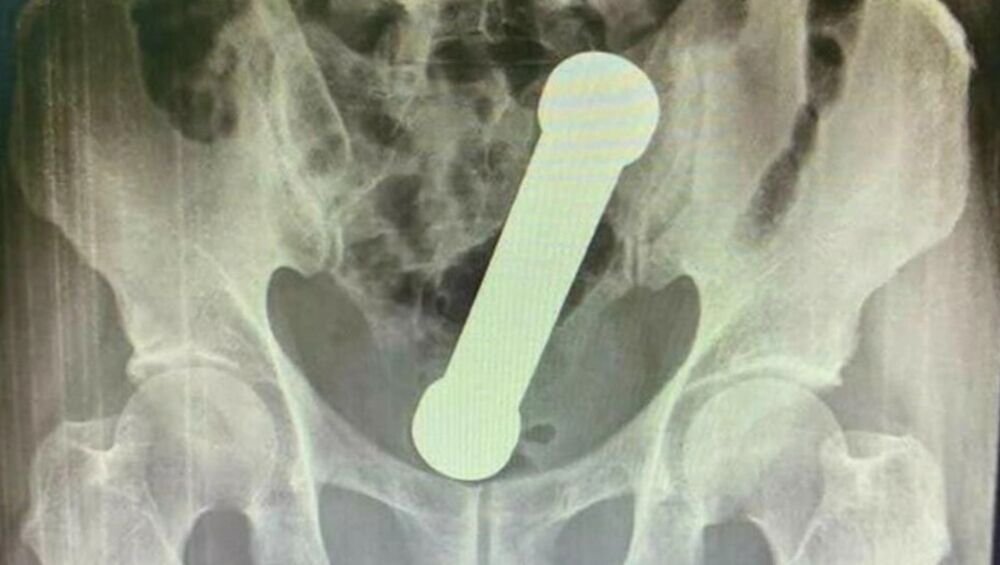

Jedan bizaran i medicinski izuzetno redak slučaj dospeo je u međunarodne naučne časopise nakon što je muškarac završio u bolnici sa tegom od 2 kilograma zaglavljenom u rektumu. Ovaj incident, koji su lekari opisali kao "medicinski izazov visokog rizika“, postao je tema naučnog rada objavljenog u International Journal of Surgery Case Reports.

Muškarac, star 54 godine iz Brazila, došao je u bolnicu nakon dva dana jakog bola, mučnine i nemogućnosti pražnjenja creva. Prema izveštaju lekara, pacijent je bio izrazito nevoljan da objasni kako je teg uopšte dospeo u njegovo telo, što je dodatno otežalo dijagnostiku.

Prvi pregled nije otkrio ništa neuobičajeno, ali je sken kasnije pokazao metalni predmet dug gotovo 20 centimetara zaglavljen na spoju debelog creva i rektuma.